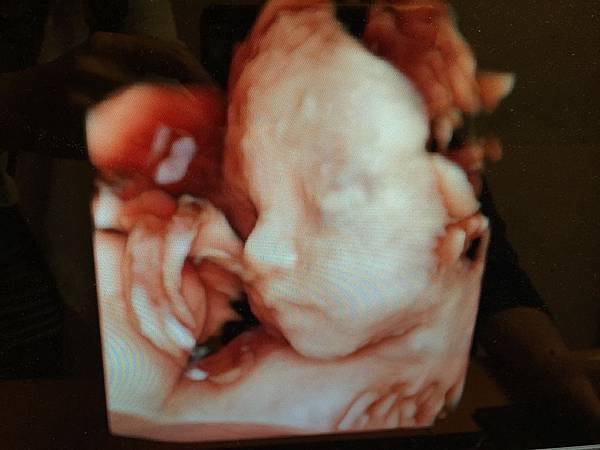

2016.04.19 24W+4

今天要做羊膜穿刺